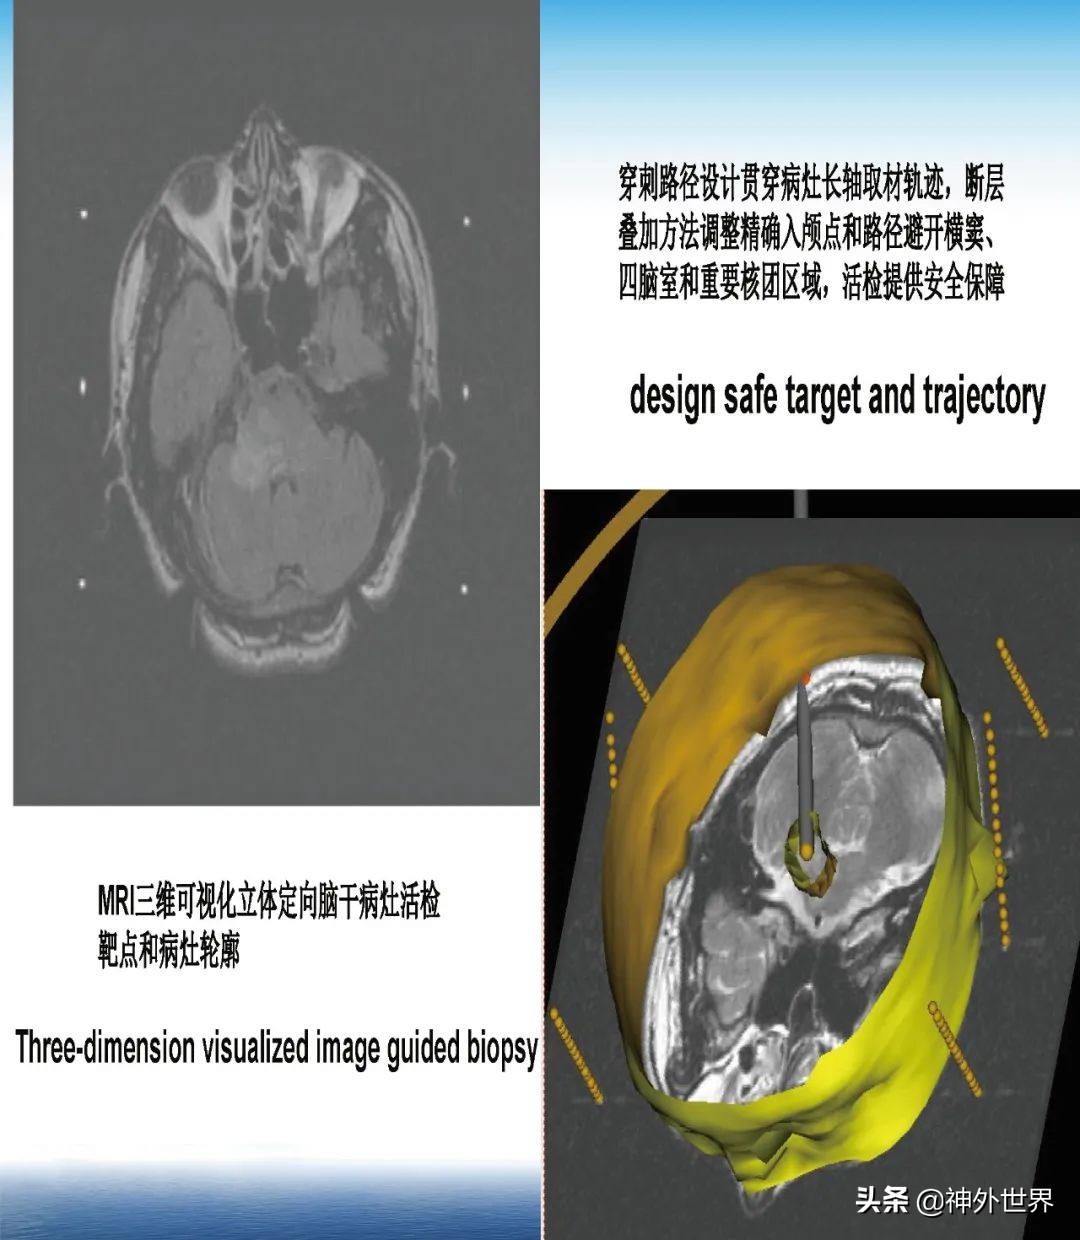

专业方向:颅内肿瘤的显微外科手术切除,颅咽管瘤综合治疗具有特色;在立体定向脑内病灶活检、立体定向清除脑干血肿、立体定向间质内放疗、机器人辅助神经外科手术方面具有专长。